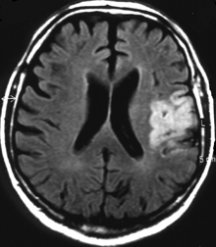

In a small pilot study of people with stroke in Germany, 20 patients treated with EPO within 7 hours of stroke later had fewer physical, speech, and memory problems and needed less day-to-day assistance than did 20 who didn’t get the hormone. People treated with EPO also tended to have smaller areas of damaged brain tissue, as measured by brain scans a month after their stroke.

People who have had the most-severe strokes seem to benefit most from treatment with EPO, reports Hannelore Ehrenreich of the Max-Planck Institute for Experimental Medicine in Göttingen, Germany. She and her colleagues published their findings in the August Molecular Medicine. The German team is now developing a trial of about 500 patients at several medical centers.

At least at this early stage in the evaluation, the benefits from EPO for stroke appear to be at least equivalent to that of tPA, Easton says. However, unlike tPA, which poses life-threatening risks of hemorrhage and thus can only be given in hospitals, EPO may be safe enough for potential stroke patients to get the drug on their way to the hospital, he adds. Since the two drugs work in different ways, physicians might also combine them.